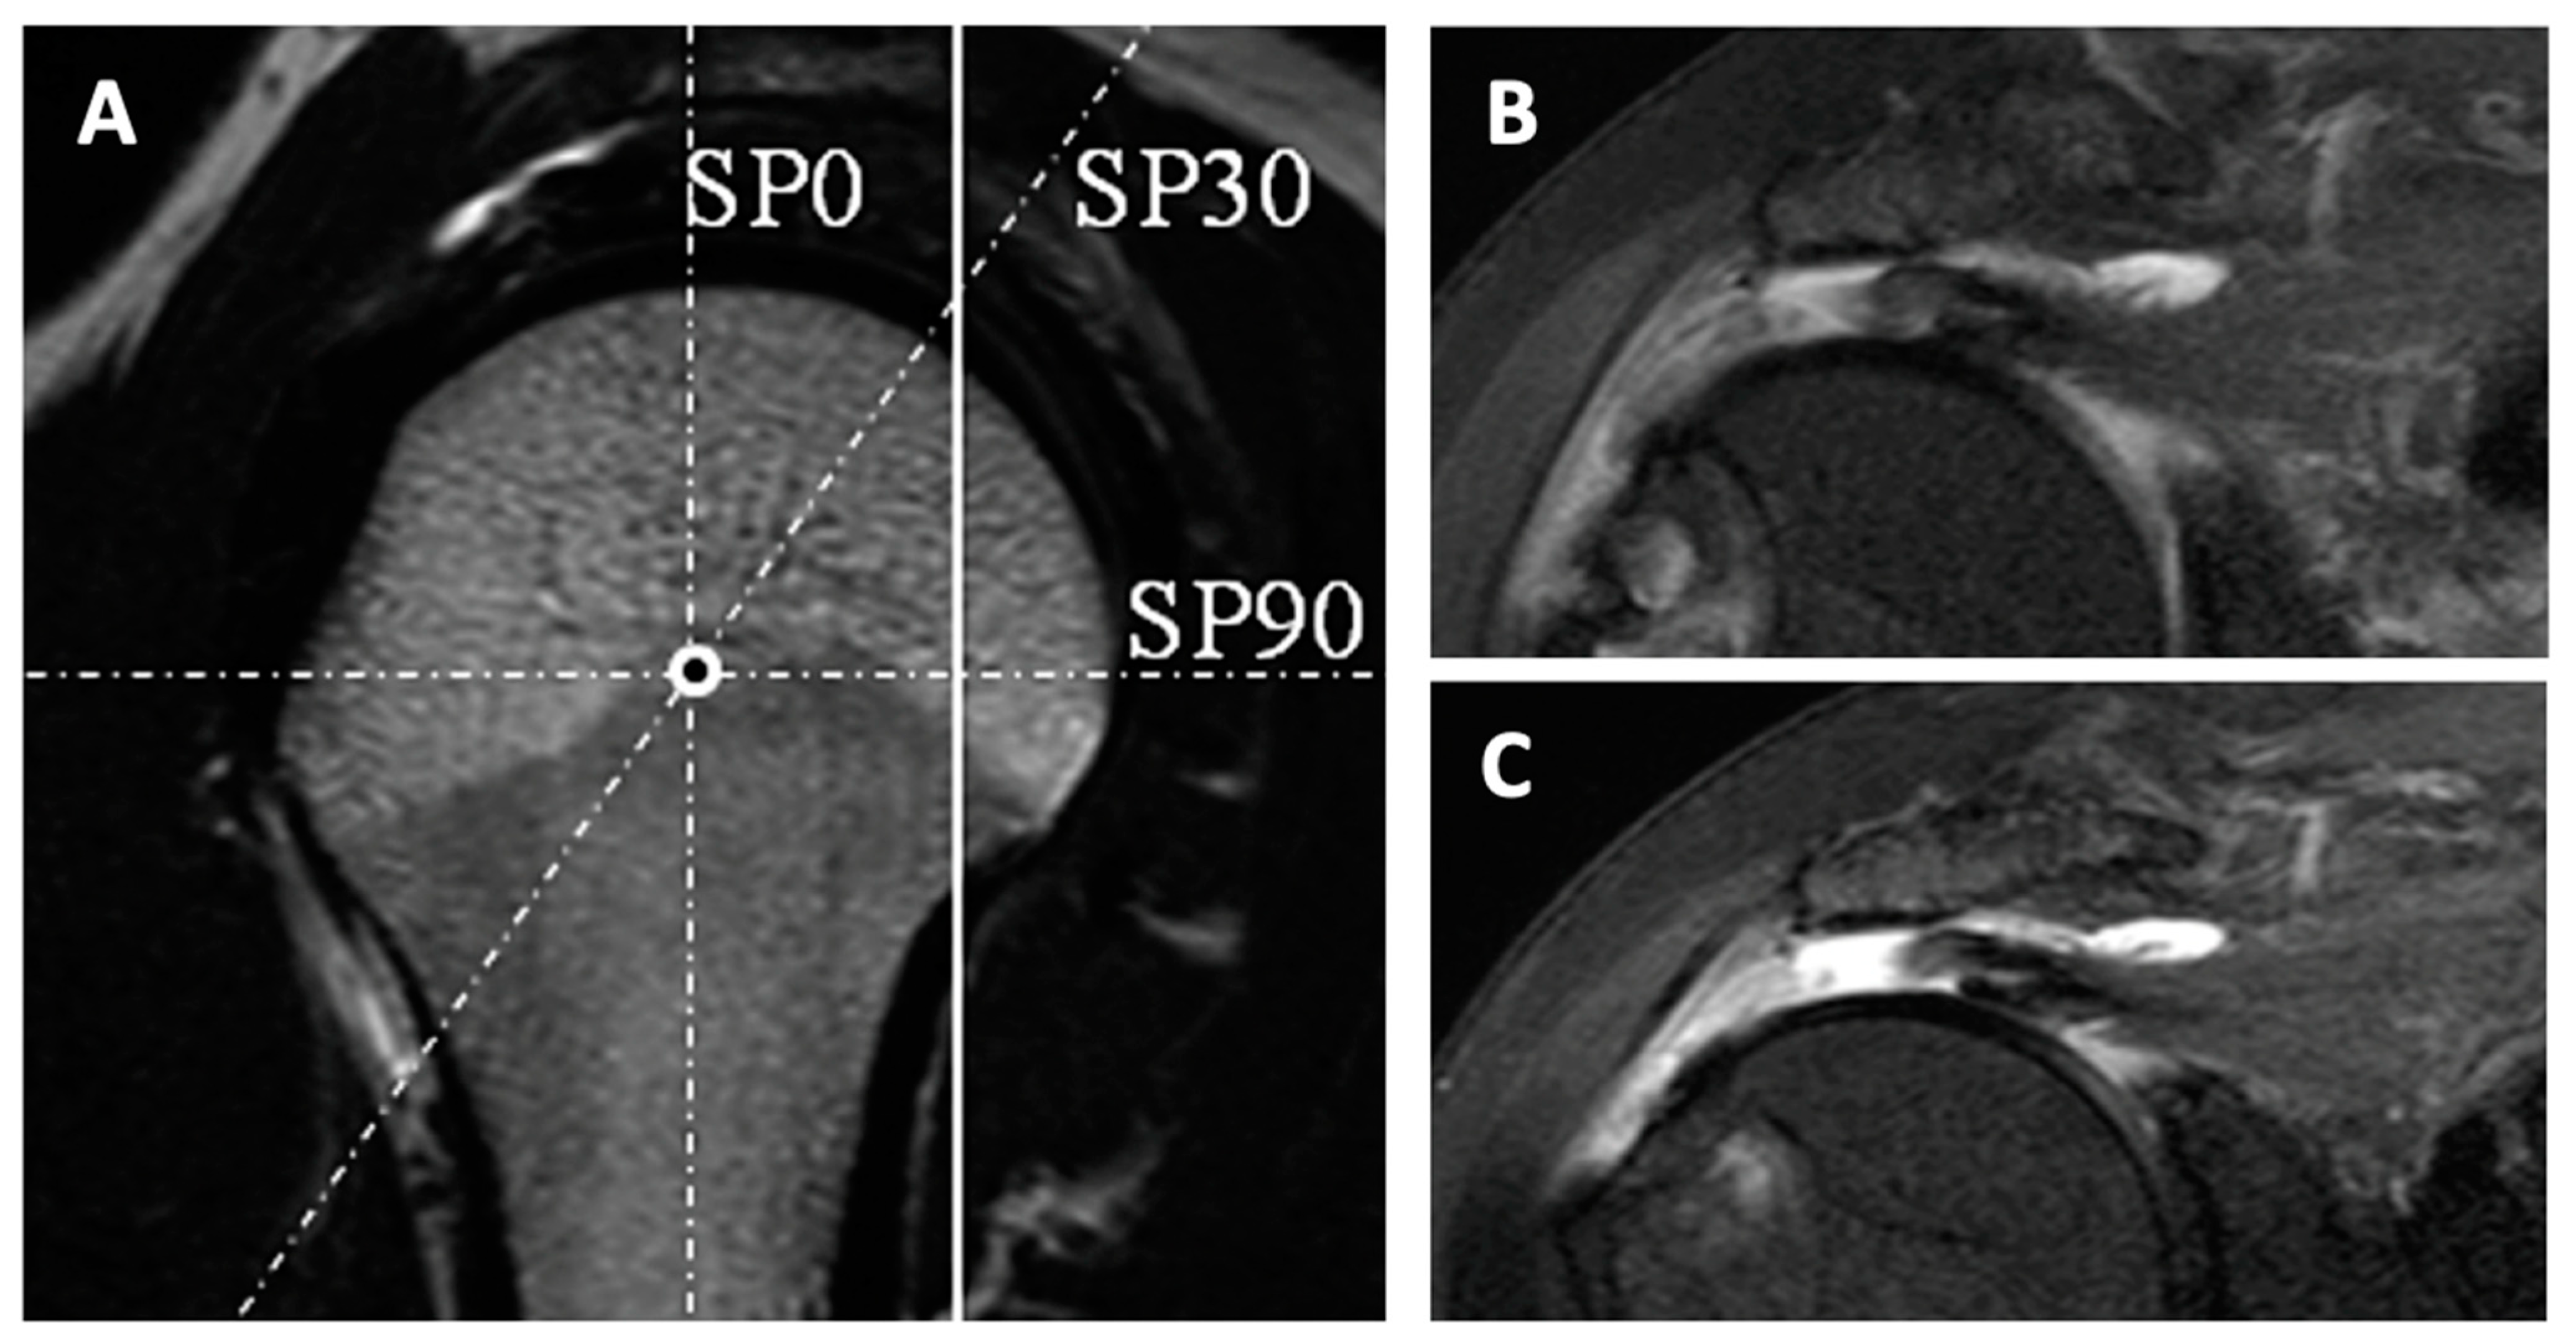

- Honda, H.; Morihara, T.; Arai, Y.; Horii, M.; Ito, H.; Furukawa, R.; Kida, Y.; Sukenari, T.; Ikoma, K.; Oda, R.; et al. Clinical application of radial magnetic resonance imaging for evaluation of rotator cuff tear. Orthop. Traumatol. Surg. Res. 2015, 101, 715–719. [Google Scholar] [CrossRef] [PubMed]

- Matsushita, R.; Yokoya, S.; Negi, H.; Matsubara, N.; Akiyama, Y.; Adachi, N. Evaluation of subscapularis tendon tears of the anterosuperior aspect using radial-sequence magnetic resonance imaging. JSES Int. 2021, 6, 97–103. [Google Scholar] [CrossRef]

- Gyftopoulos, S.; Beltran, L.S.; Gibbs, K.; Jazrawi, L.; Berman, P.; Babb, J.; Meislin, R. Rotator cuff tear shape characterization: A comparison of two-dimensional imaging and three-dimensional magnetic resonance reconstructions. J. Shoulder Elb. Surg. 2015, 25, 22–30. [Google Scholar] [CrossRef]